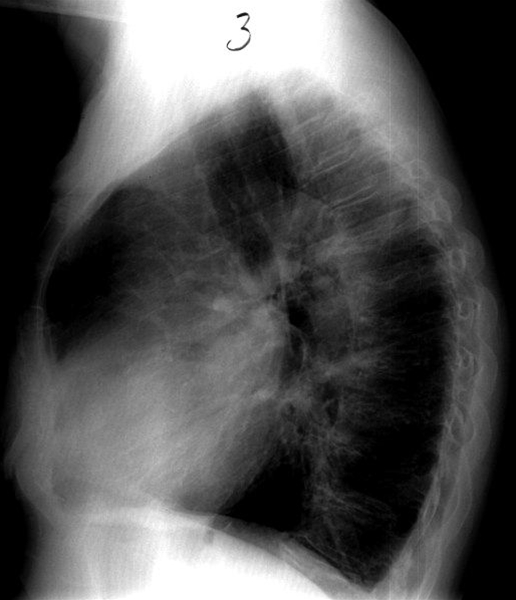

Cor pulmonale, sideoptagelse

Cor pulmonale (hjerteforstørrelse på grund af forhøjet vaskulær modstand i lungekredsløbet).

Forstørret højre hjertehalvdel.

Bifund: Tydelig forkalket aortabue.